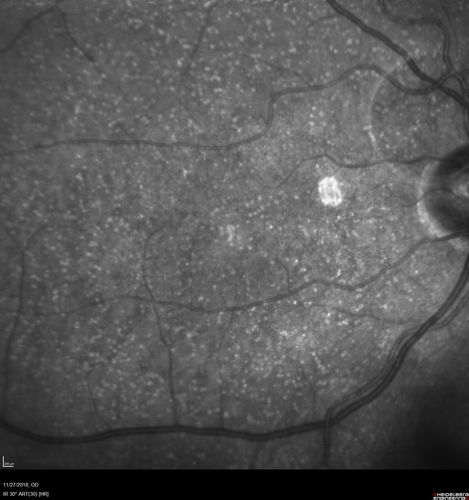

Unusual Intraretinal Deposits

71 year old diabetic man on dialysis with 20/20 vision and intraretinal deposits. Recent 150 lb weight loss, on dialysis, see album properties for full history